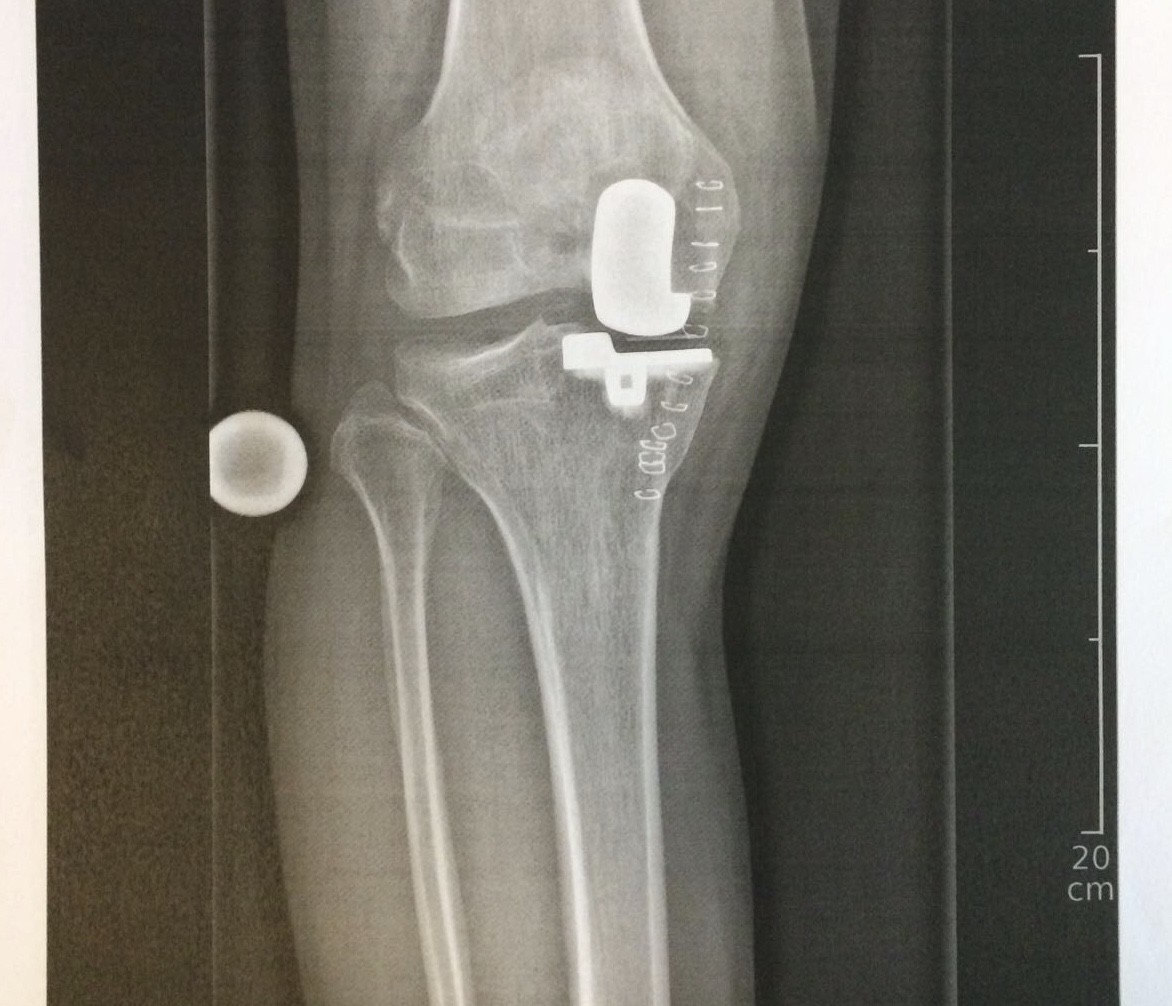

Hintergrund: Normalerweise fahre ich im Sommer nicht Ski. Ich weiss aber seit einigen Wochen, dass ich dieses Jahr ein neues Kniegelenk einsetzen lassen muss. Meine Ärzte sagen, das linke Knie sei im Eimer; das gehe nur noch mit einer Vollprothese. Diese wird auf Mass gefertigt und ist in ca. 8 Wochen bereit. Das ganze ist die Folge eines Sturzes auf der Piste anno 2001.

@jwahl - Danke vielmals! Das ganze wird offenbar etwa so ablaufen - mit einer Massprothese sollte ich dann einige Jahre Ruhe haben.

Fazit: Mehr als würdiger Abschluss für mein Kniegelenk, das ab Mitte September zu grossen Teilen aus einer Kobalt-Chrom-Molybdän-Legierung und ultrahochmolekularem Polyethylen bestehen wird. Danke für tausende Pistenkilometer in fast 50 Jahren, wertes linkes Knie - von den Buckelpisten der 1970er am benzinbetriebenen Skilift in Surrein zu den Carvingautobahnen der Neuzeit.

Was ich mich wundere: Offenbar hast Du mit Deinem lädierten Knie mehrfach den Tunnel und den Rückweg zum TS gemeistert, aber ich habe nirgends von „Qual“ oder so gelesen. Wenn ich mich an die Zeit vor meiner Knieprothese (2015) erinnere, da hatte ich Skigebiete mit Laufwegen total gemieden, weil die Schmerzen unerträglich waren und wäre deswegen niemals nach Zermatt zum Sommerski. Dafür bin ich Vortag (!) der Operation Ende September nochmal auf den Stubaier Gletscher, um Abschied zu nehmen und nur fünf Wochen später, anfangs November stand ich bereits in Gurgl wieder mit künstlichem Gelenk auf den Skiern. Allerdings war/ist es bei mir nur eine halbe Prothese.

Nicht ganz. Mein neues "Knie" wird aufgrund des CT auf Mass gefertigt, nix "ab Stange". Dazu kommen im Paket auch die extra gefertigten Schnittschablonen. Mehr dazu in diesem Video. Gerade bei einem jüngeren Patienten (also ca. unter 60 in diesem Fall) nimmt man keine Konfektionsware, um möglichst viel Knochen für eine allfällige Revision zu "sparen".

Ich war bei der Operation 44 Jahre alt, also in diesem Kontext sogar sehr jung. Genau aus diesem Grunde, wurde - so mein Arzt - ein sehr dünnes Implantat verwendet, damit der Knochen für einen allfälligen Ersatz nach prognostizierten 25-30 Jahren noch genügend dick ist.

03C74715-64B6-41EF-A5A2-1FA651175703.jpeg

03C74715-64B6-41EF-A5A2-1FA651175703.jpeg (197.17 KiB) 9264 mal betrachtet

OT: Falls es jemanden interessiert, wie die Knieprothesen-Story weitergegangen ist, welche diesen Bericht sozusagen ausgelöst hat... hier ist die ganze Geschichte (Disclaimer: in der Mitte hat es blutige OP-Fotos). Das Implantat sitzt, ich bin seit vorgestern wieder zu Hause. Und wenn alles ideal läuft, stehe ich im Dezember wieder auf der Piste, und sonst eben etwas später.